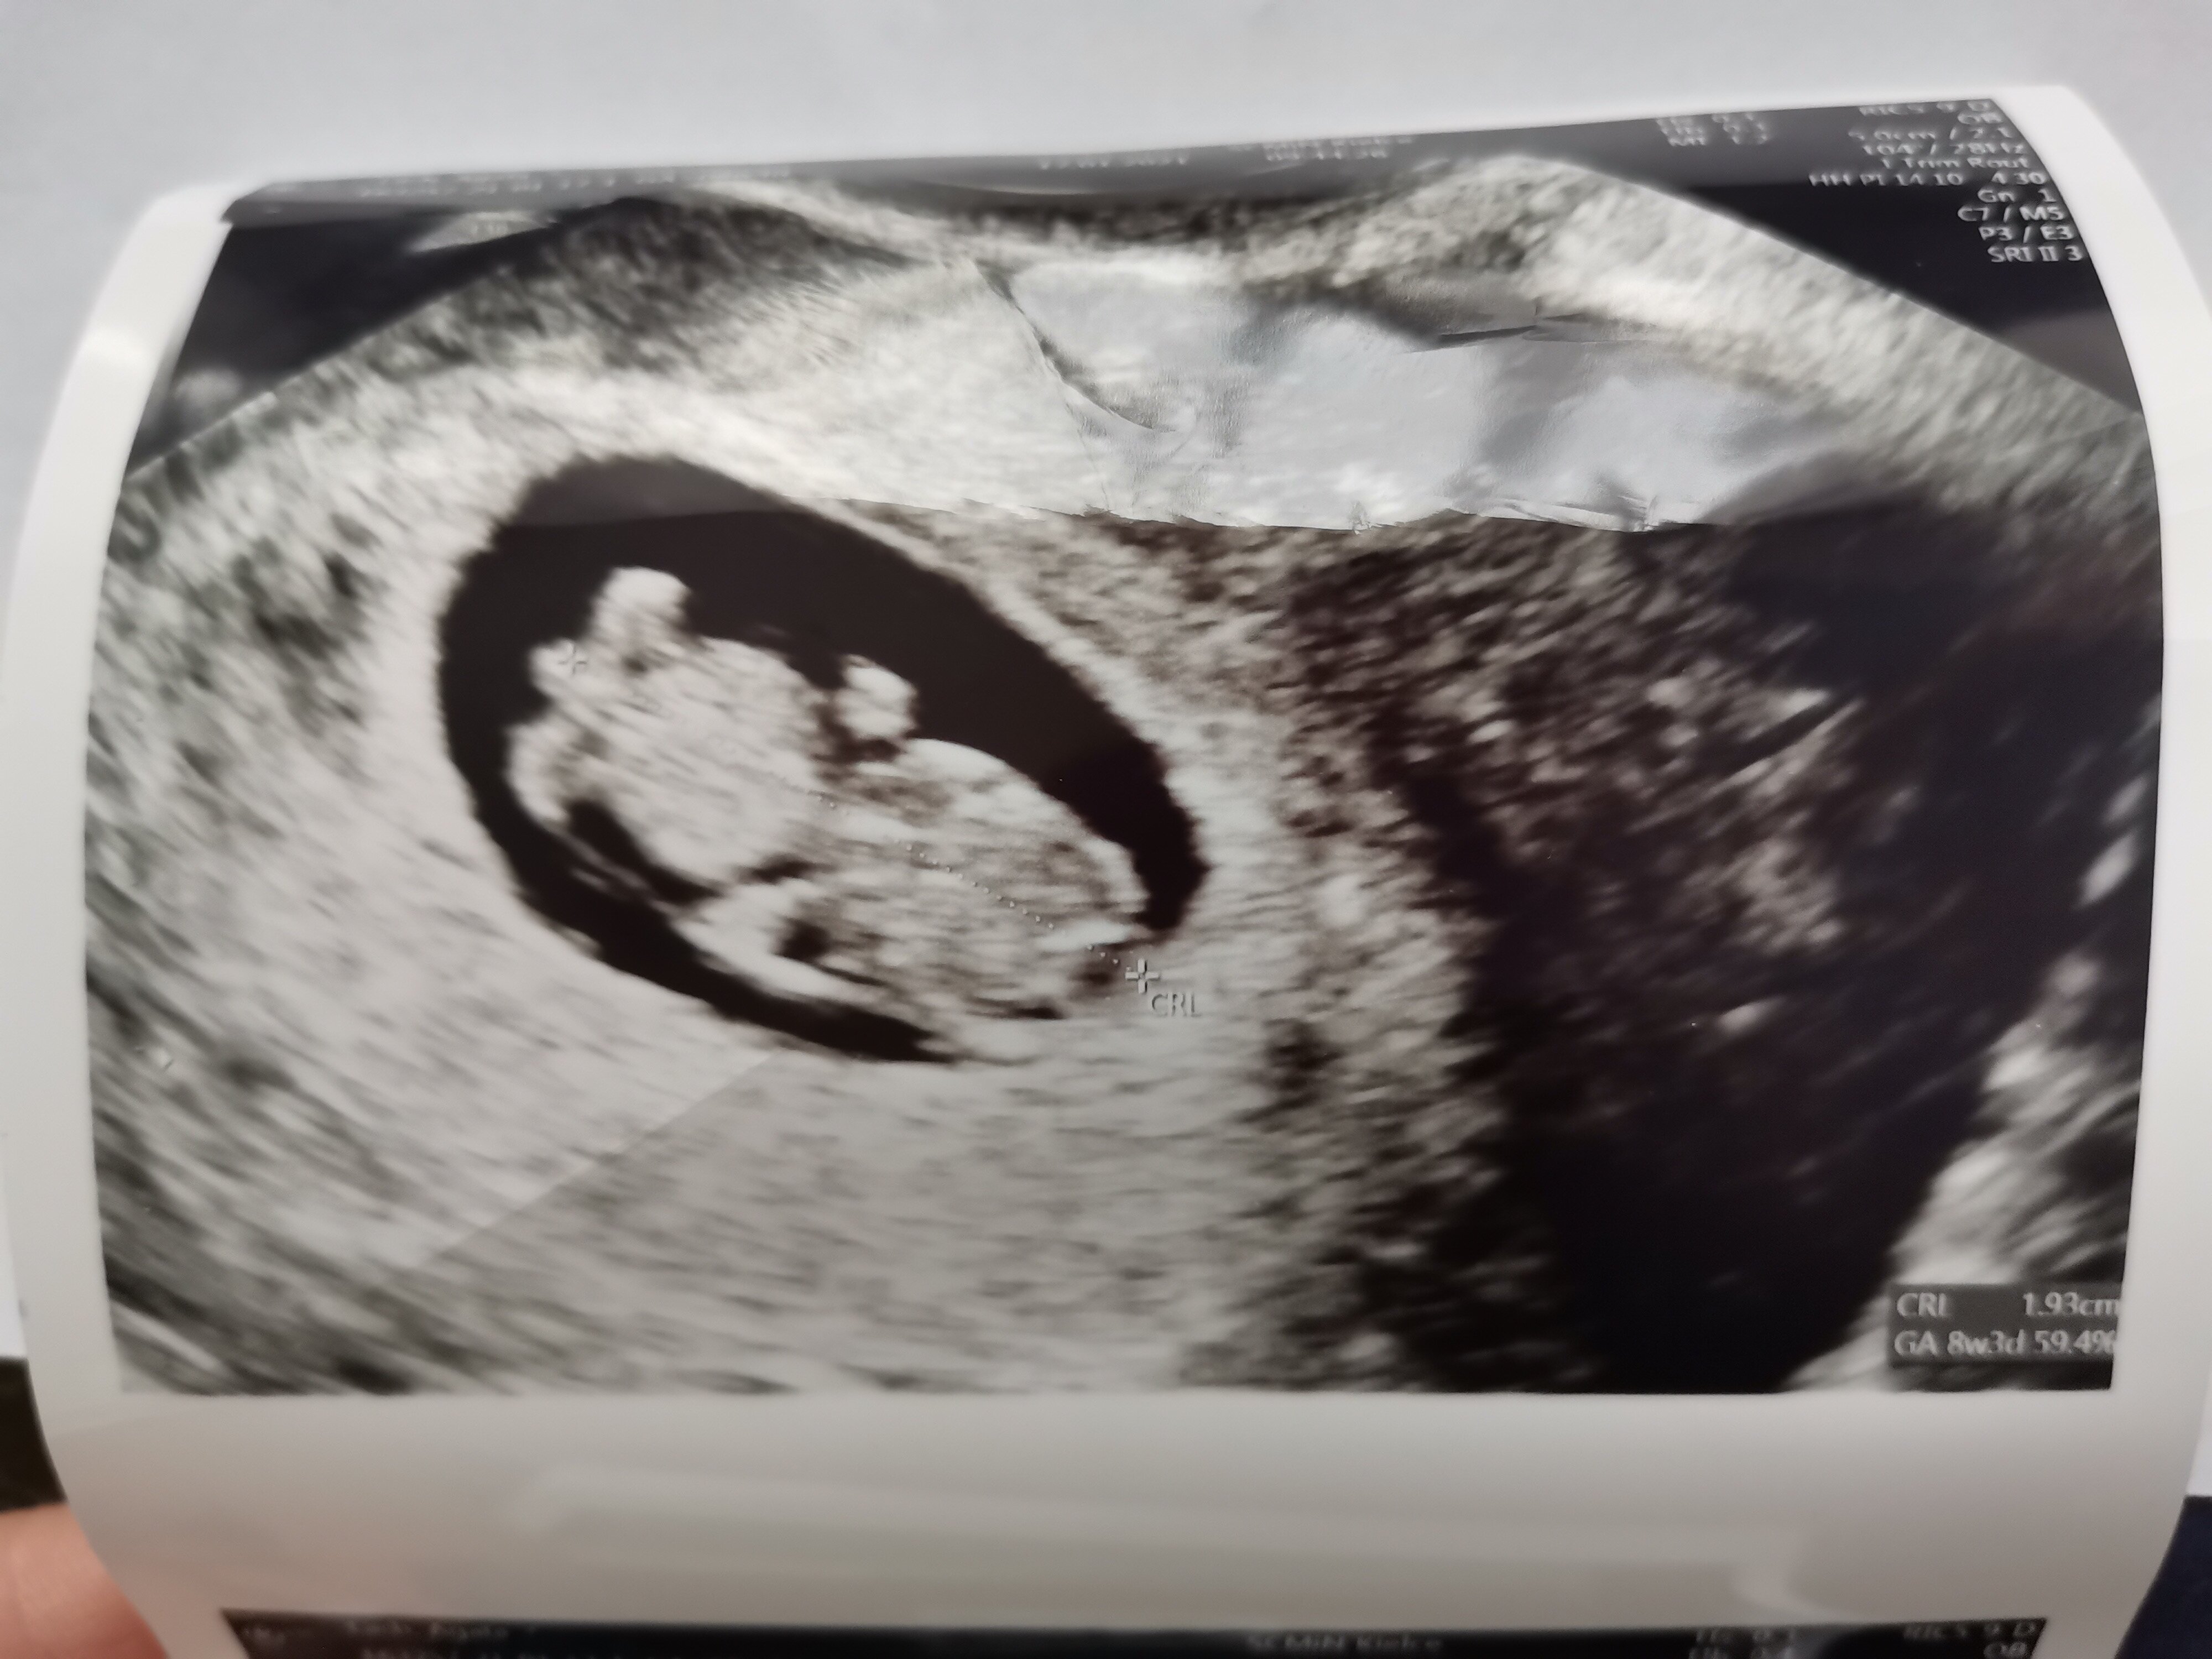

Hej, ja też po zimowym spacerze 😁 Ostatnio bolał mnie pęcherz i dzwoniłam do lekarza czy mogę wziąć jakieś leki bo żurawina nie przynosiła poprawy. Dziś miał dyżur w szpitalu i kazał przyjechać. Miałam pobrana krew i mocz do badania. Zrobił USG widziałam dzidziusia ma prawie 2cm i jest wszystko dobrze 😀 Dzisiejsza wizyta przyniosła mi najwięcej radości i nastawila pozytywnie 🥰 Dziś 8 + 3/4 i na zdjęciu jux widać pięknie małego czlowieczka ❤️ Spróbuję dodać zdjęcie może się uda 😀 Umówiłam się też na usg prenatalne 11 lutego a normalna wizyta 26 stycznia 🙂

IMG_20210117_140418.jpg

Hej, ja też po zimowym spacerze 😁 Ostatnio bolał mnie pęcherz i dzwoniłam do lekarza czy mogę wziąć jakieś leki bo żurawina nie przynosiła poprawy. Dziś miał dyżur w szpitalu i kazał przyjechać. Miałam pobrana krew i mocz do badania. Zrobił USG widziałam dzidziusia ma prawie 2cm i jest wszystko dobrze 😀 Dzisiejsza wizyta przyniosła mi najwięcej radości i nastawila pozytywnie 🥰 Dziś 8 + 3/4 i na zdjęciu jux widać pięknie małego czlowieczka ❤️ Spróbuję dodać zdjęcie może się uda 😀 Umówiłam się też na usg prenatalne 11 lutego a normalna wizyta 26 stycznia 🙂Zobacz załącznik 1227899